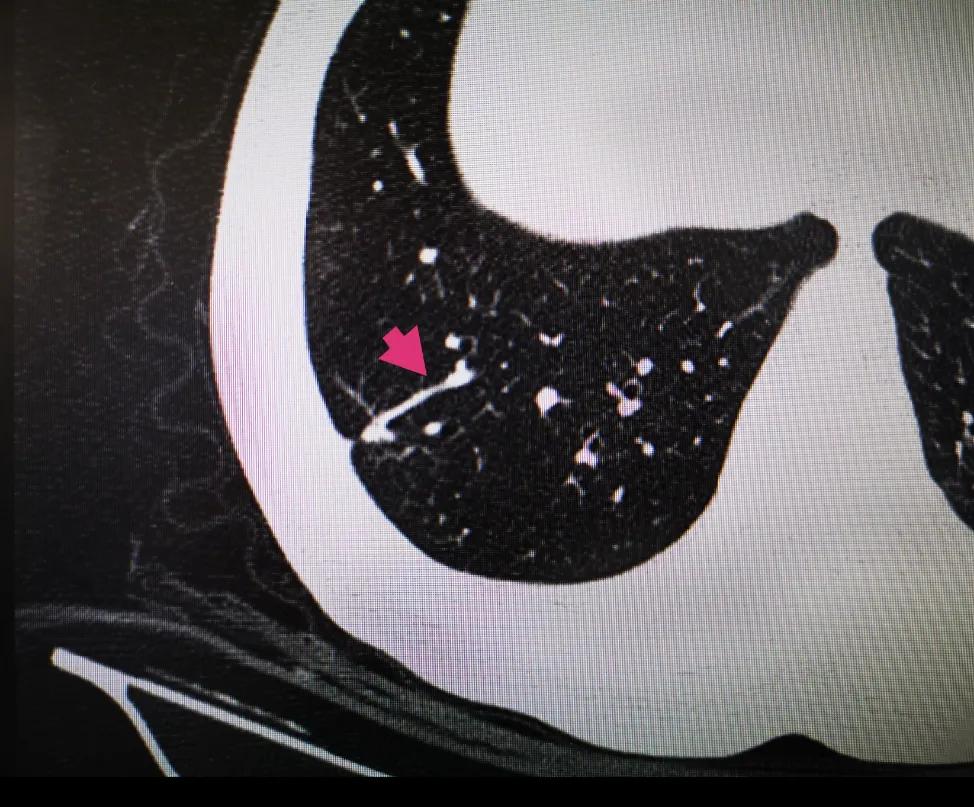

观察肺结节的变化可以通过定期进行胸部CT扫描或X射线检查来实现。这些检查可以帮助医生了解结节的大小、形态和变化情况。如果结节在短时间内有显著增大或出现其他异常改变,可能需要进一步进行检查,例如PET-CT扫描或活检等。

需要注意的是,肺结节的类型需要通过影像学检查(如CT扫描)来确定,但仅通过CT影像无法确定结节的性质,还需要结合其他临床信息以及必要的生物组织学检查(如活检)来做出最终的诊断。